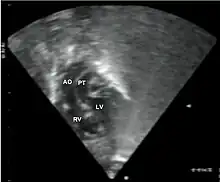

Echocardiogram: An echocardiogram is an ultrasound of the heart which accurately assesses the heart’s structure and function, and can show the specific features of TGA, if present. This imaging modality allows for the definitive diagnosis of TGA to be made. [8]

Echocardiography of a complex transposition with a ventricular septal defect and pulmonary stenosis.

Abbreviations: LV and RV=left and right ventricle, PT=pulmonary trunk, VSD=ventricular septal defect, PS=pulmonary stenosis. -